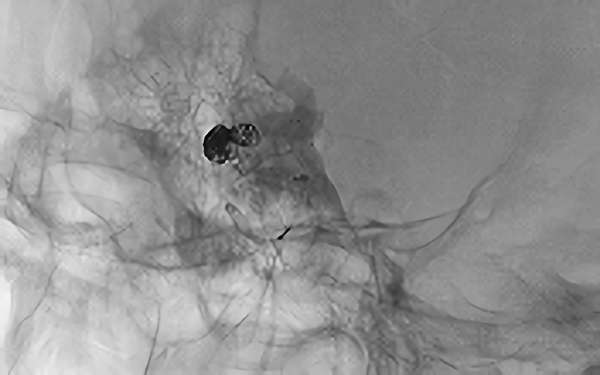

No.1631 手術中